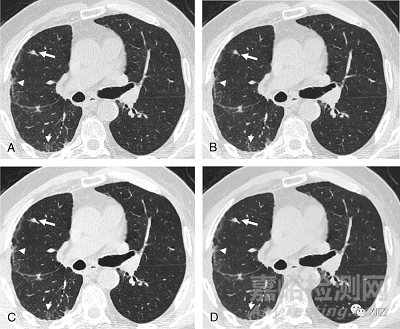

最近,基于神經(jīng)網(wǎng)絡(luò)的深度學(xué)習(xí)的圖像重建(DLIR)算法正在出現(xiàn):GE Healthcare的TrueFidelity(TF)和Canon Medical Systems的Advanced Intelligent Clear-IQ Engine(AiCE)。圖2、3和4顯示了用FBP、ASIR-V、TF和iDose4在不同水平上重建的CT掃描的例子。

圖4 用不同級別的iDose4算法重建的CT圖像的比較。一名患有間皮瘤的63歲男子的軸向薄層非增強(qiáng)胸部CT掃描,顯示右肺中有一個(gè)非鈣化的實(shí)質(zhì)結(jié)節(jié)(白色箭頭)和胸膜下結(jié)構(gòu)扭曲(白色箭頭)。胸部CT是在100 kVp下采集的,具有管電流調(diào)制(mAs范圍,109–220)。使用iDose4算法在不同水平重建圖像:(A)iDose1、(B)iDoe3、(C)iDos5和(D)iDose7。高強(qiáng)度IR保持高對比度和空間分辨率,為減少輻射劑量鋪平了道路。